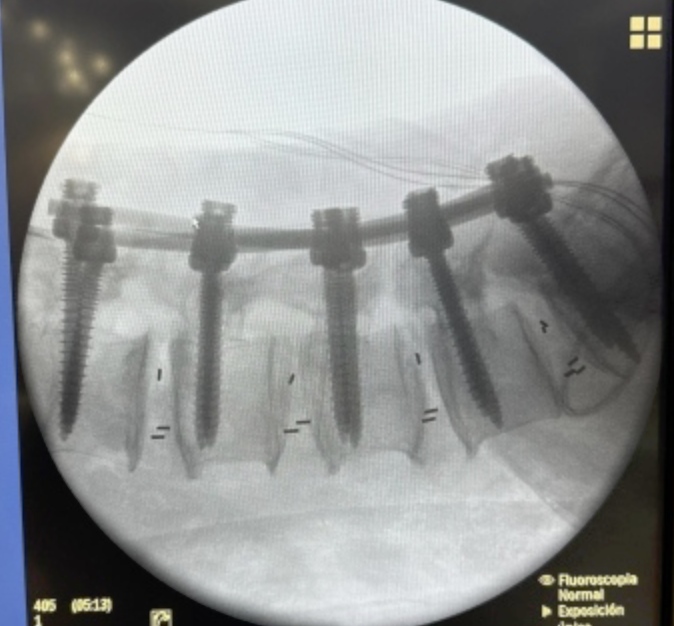

SURGERIES